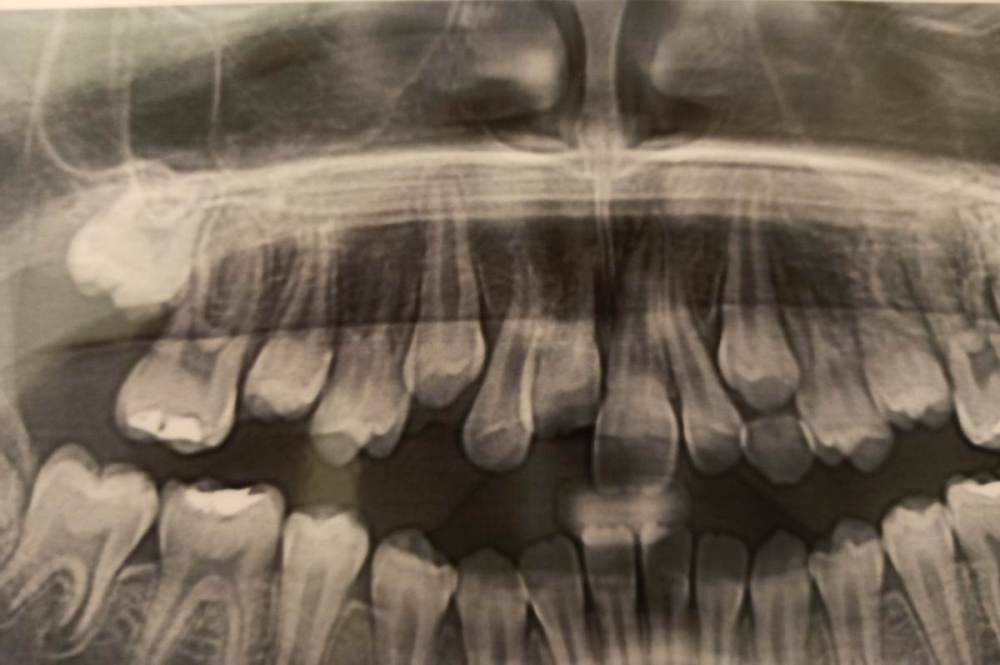

wladdX Опубликовано 4 июля, 2021 Поделиться Опубликовано 4 июля, 2021 Насколько могу судить по приложенным скринам, резорбция корня всё же есть. Судя по Вашему рассказу, проведённая коллегами работа была верной, результат весьма неплохой. Рассчитывать на длительное пребывание зуба 11 в челюсти не приходится. Когда-то его придётся удалить. 1 1 Ссылка на комментарий

Pole4ka Опубликовано 4 июля, 2021 Автор Поделиться Опубликовано 4 июля, 2021 38 минут назад, wladdX сказал: Насколько могу судить по приложенным скринам, резорбция корня всё же есть. Судя по Вашему рассказу, проведённая коллегами работа была верной, результат весьма неплохой. Рассчитывать на длительное пребывание зуба 11 в челюсти не приходится. Когда-то его придётся удалить. Спасибо большое за Ваше мнение и отклик! Нам бы дотянуть до момента, когда можно будет ставить имплант. Честно говоря, особой разницы между прошлогодним снимком (нижним среди снимков) и панорамным не вижу, поэтому возникла надежда, что резорбция приостановлена. А анкелоза нет? Спасибо! @wladdX Спасибо!!! Ссылка на комментарий

wladdX Опубликовано 5 июля, 2021 Поделиться Опубликовано 5 июля, 2021 Резорбция корня + вертикальное расположение = анкилоз. То что зуб был с несформированной верхушкой корня помогло ему простоять так долго после реплантации в растущей челюстной кости. Конечно, хорошо бы, чтоб зуб смог простоять до имплантации, но на мой взгляд это маловероятно. 1 1 Ссылка на комментарий

Pole4ka Опубликовано 6 июля, 2021 Автор Поделиться Опубликовано 6 июля, 2021 @wladdX @wladdX @wladdX 04.07.2021 в 21:44, wladdX сказал: 04.07.2021 в 22:25, Pole4ka сказал: @wladdX 20 часов назад, wladdX сказал: Резорбция корня + вертикальное расположение = анкилоз. То что зуб был с несформированной верхушкой корня помогло ему простоять так долго после реплантации в растущей челюстной кости. Конечно, хорошо бы, чтоб зуб смог простоять до имплантации, но на мой взгляд это маловероятно. Очень жаль, что такой неутешительные прогноз. Нам бы конечно дотянуть до имплантации. Но ведь за год изменений между двумя снимками практически нет, даже внешне (на снимках) стало чуточку лучше. И зуб не изменил цвет и неподвижный. Или это вообще ни о чем не говорит? Спасибо! Вверху 2021 год - панорамный снимок, внизу 2020 - КТ Ссылка на комментарий

Bier Опубликовано 6 июля, 2021 Поделиться Опубликовано 6 июля, 2021 Я вас не порадую: 1. Зуб анкилозирован. 3 часа в физрастворе = нет шансов на реваскуляризацию пульпы и связки. Судя по вашим снимкам однозначно анкилозирование. 2. Что делать теперь и почему: Зуб начал отставать в росте, еще через несколько лет это превратится в нерешаемую эстетическую проблему (вся челюсть будет расти, а зуб и участок челюсти с зубом - нет). Необходимо провести операцию декоронации (спилить коронковую часть зуба глубже уровня костной ткани, удалить то, что осталось от пульпы и дать так зажить. Остатки корня резорбируются сами с замещением на кость. Зато челюсть будет расти вместе с отстальными зубами. восстановить зуб временно на пластике (съемной) потом на брекетах. Имплантация желательно не раньше 21 года. Оставлять так нельзя! Ссылка на комментарий